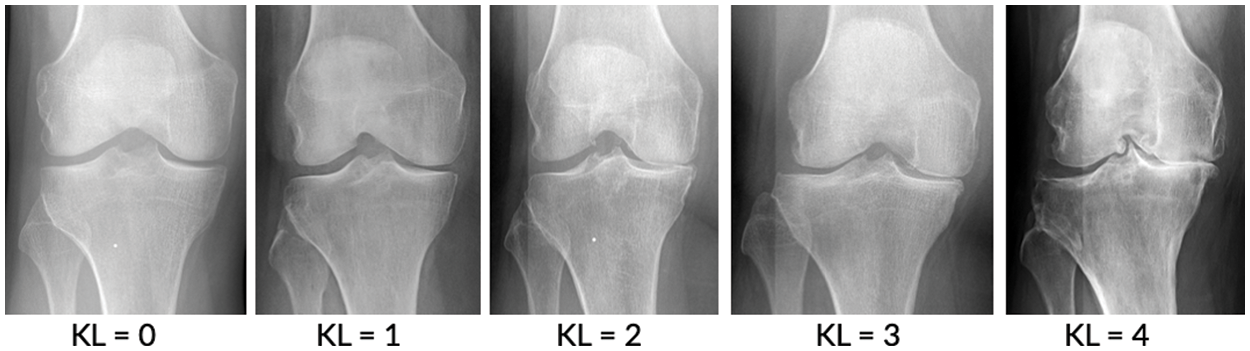

The human body is composed of numerous joints that allow it to move. Articular cartilage, which is the most vital tissue for maintaining normal joint function, is located between the joints to prevent the bones from colliding. The cartilage is indispensable for body movement and is one of the largest and most complex joints in the body. Cartilage is consistently used in everyday life, thus natural wear and tear during childhood, adolescence and old age can lead to symptoms based on a variety of causes; and physical-contact athletes, as well as age, are at increased risk of cartilage rupture. Activity and age are common causes, and degenerative arthritis (also known as osteoarthritis) may occur based on a combination of additional factors, including family history, obesity, diabetes, synovitis, systemic inflammatory mediators, innate immunity, lower body alignment, joint shape, and inflammation due to dysplasia, trauma and metabolic syndrome. It is the most common joint disease that can occur in anyone, and it is a major cause of disability worldwide, and the number of people suffering from the disease will continue to grow owing to aging populations and increased obesity. These causes can be divided into correctable and uncorrectable causes. Among the modifiable factors, the most common symptom is obesity, with 1 pound (0.45 kg) of weight applying 2 to 4 pounds (0.9 to 1.8 kg) to the knee, and excessive body weight increases joint loading causing detrimental and adverse effects on the weight-bearing joints. Uncorrectable causes include genetic variants and congenital factors, and the most common risk factor is age. In Korea, more than 80% of patients over the age of 55 or almost all patients over the age of 75 are diagnosed with osteoarthritis of the knee through radiographic examination, as shown in Fig. 1. The diagnosis is based on the visual changes shown in Fig. 2, such as localized articular cartilage and joint deformity, and is based on the patient's opinion of chronic pain, stiffness, and limited range of movement of the joint. If the cartilage suffers from severe wear and tear, it will cease to function normally, necessitating surgical or nonsurgical treatment. Nonsurgical treatment includes methods such as physical therapy, exercise therapy, and medication. Surgical treatments, such as knee osteotomy and artificial joint replacement, are performed in cases in which the pain is too severe to maintain the lifestyle, the pain does not improve even after six months of nonsurgical treatment, the structural deformation or instability of the joint is severe, or restrictions in range of motion are severe. However, there is a risk of infection during surgical treatment, which could necessitate re-surgery. Particularly in the case of artificial joint replacement treatment, as shown in Fig. 3, side effects, such as pain and functional failure, may be accompanied by structural instability after treatment. Owing to the limitations of surgical treatment, it is less burdensome to seek improvement through nonsurgical treatment with low side effects, and accurate diagnosis of arthritis is critical for early treatment to prevent surgical treatment. However, owing to the significant cost and time required to receive a diagnosis and a doctor’s opinion through the simple X-ray imaging process, most patients often go to the hospital only after a severe course and when everyday life is not possible. The scientific and logical evidence for the diagnosis and treatment of knee osteoarthritis is therefore increased, and evidence for standardized diagnostic and treatment methods that can be used in clinical settings must be performed [1–4].

Figure 1: Stage of knee osteoarthritis [7]

To apply deep learning to the actual medical world, it is necessary to show considerable accuracy, and scientific and logical evidence is required in the diagnosis process. Deep learning models for segmenting lesion areas or classifying lesion grades using X-ray images have been popularly adopted not only for degenerative arthritis problems but also for other problems, such as tuberculosis diagnosis [4]. Currently, research into medical artificial intelligence is actively being conducted. It is expected that through the various standardized diagnosis methods proposed in studies [5,6], doctors will be able to use more objective indicators to make faster and more accurate diagnoses. Therefore, if more accurate predictions can be made, deep learning can be used to prevent disease caused by degenerative arthritis. The existing procedure for diagnosing osteoarthritis is to first take radiographic images, as shown in Fig. 1, and then to consider the resulting images, which show the gradual reduction of joint spacing and deepening shadows of the bones under the cartilage. Furthermore, a questionnaire is administered to patients when determining the grade of osteoarthritis. Because this procedure allows for the diagnosis of osteoarthritis based on visual changes similar to those shown in Fig. 2, studies have been widely conducted to determine the grade of osteoarthritis using accumulated knee radiology images to train a deep learning model. Although deep learning models based on these visual changes enable information transfer to objective indicators, extensive research has been performed to improve the accuracy of osteoarthritis classification, which is necessary for practical use.

This study focused on degenerative arthritis, and the Kellgren–Lawrence (K–L) grade, which is the most commonly used grade classification index for degenerative arthritis diagnosis according to cartilage wear in the knee joint, was used as a reference. The K–L grade is divided into five classes, as shown in Fig. 1 and Table 1.